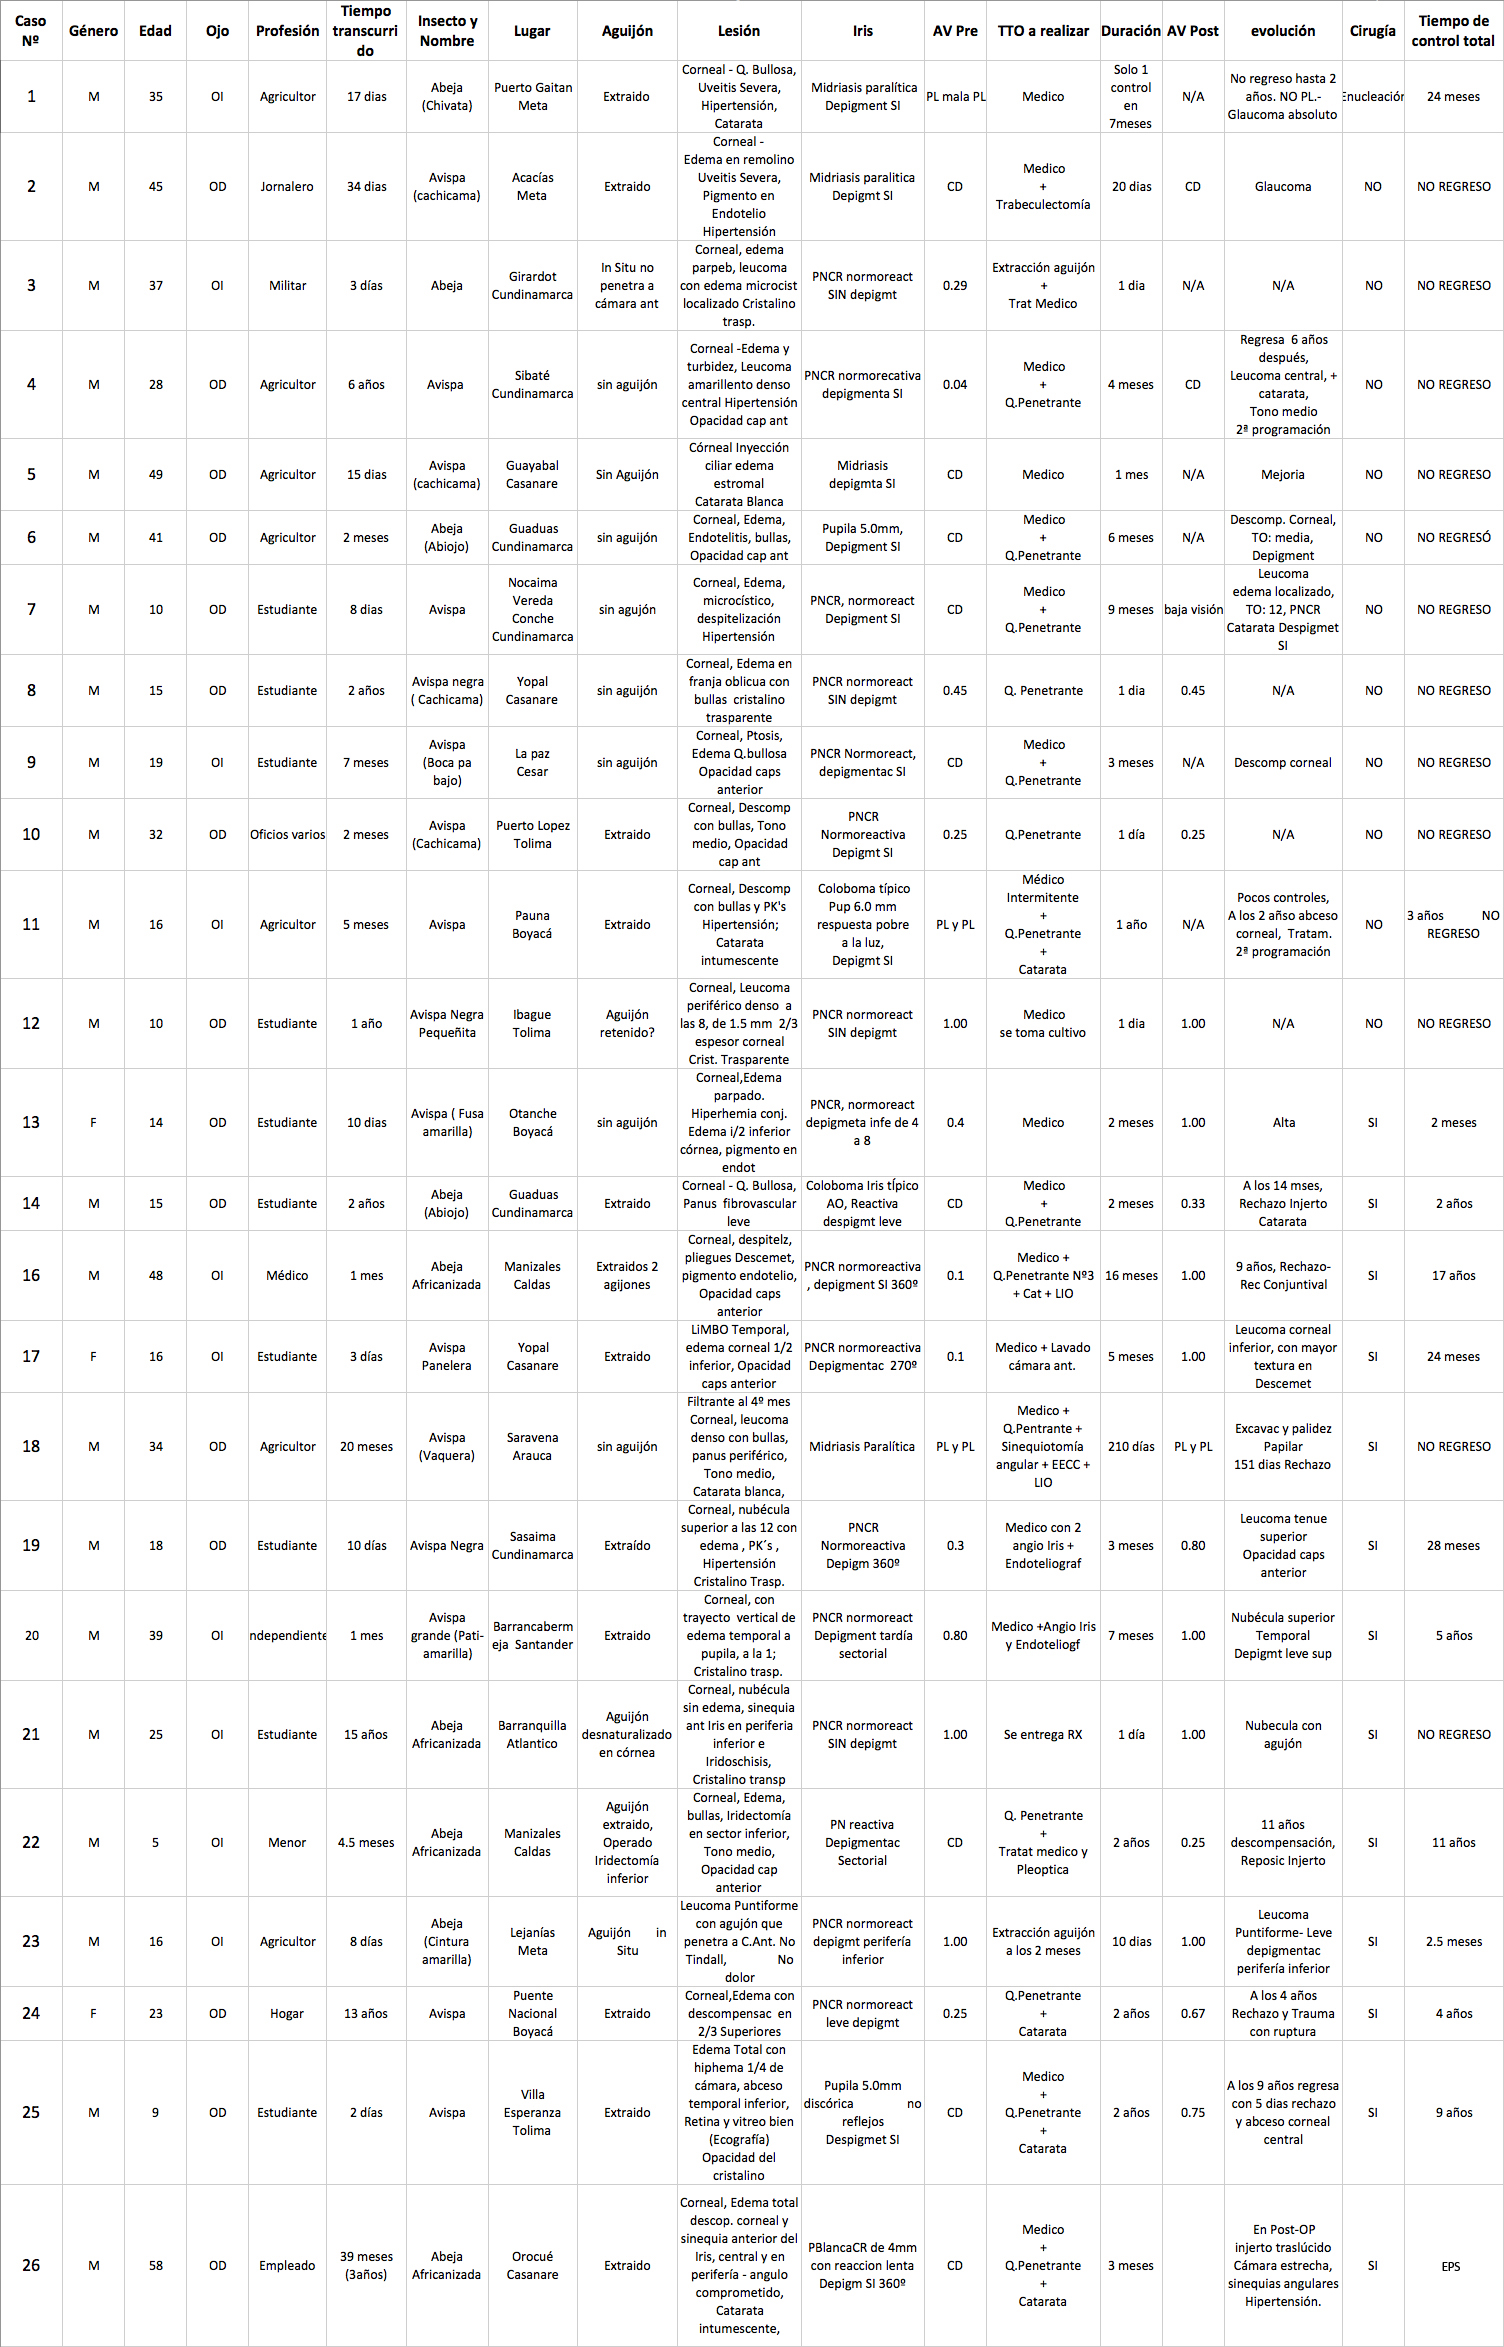

Caso No 6.

Paciente agricultor de Guaduas 41 años Diabético, quien 2 meses antes de la consulta sufrió picadura de abeja llamada “ Abiojo” en el Ojo Derecho. Recibio tratamiento a partir del 4o día con Atropina 3 al día Decadron IM 1 al día, Flucon cada 4 horas

Al examen: Edema corneal con pliegues profundos, areas desepitelizadas y bullas, Endotelitis. Neovascularización corneal temporal inferior; Iris marrón blanquecino por pérdida marcada de pigmento, pupila de 5.0mm, opacidad en cápsula anterior. Tension Ocular digital media (Foto No 10).

Foto 10 - Foto inicial con bullas y neovascularización

Refracción: No Rx que ayude AVcc: CD

Conducta: Decadron s/c cada 10 días( 6 amp), NaCl 3 al dia,, Maxidex 3 al dia, Atropina 1 al dia con controles cada 10 dias- Mas adelante Queratoplastia Penetrante.

Ultimo control a los 6 meses: Descompensación corneal, con reducción del area de leucoma; panus fantasma, despìgmentación del Iris, mantener Cetapred 2 al día y NaCl 3 al día- (Foto No 11) NO REGRESÓ

Foto 11 - Ojo mas tranquilo con descompensación corneal

Caso No10.

Paciente masculino quien realiza o cios varios, 32 años ( Tolima - Puerto Lopez) . Hace 2 meses picadura de avispa Cachicama en el OD - El aguijón fue extraído. Fue tratado con Maxidex durante 20 días

Refracción mani esta: OD: AVsc: CD AVcc: CD OI: AVsc: 0.25 No rx que ayude AVcc: 0.25

Al examen: OD Edema corneal con Queratopatía bullosa, “Atro a del Iris”, Opacidad subcapsular anterior;. Tensión ocular digital media. Secuelas tóxicas de picadura (Foto No12)

Foto 12 - Foto con edema total de la córnea, despigmentación del Iris y opacidad subcapsular anterior

En el OI: Antecedente de trauma craneoencefálico 20 años antes, con la rama de un arbol. Córnea con nubéculas múltiples puntiformes; Catarata subcapsular anterior y posterior en roseta. Tensión ocular 12, Recesión angular, polo posterior bien.

Se programa para Queratoplastia penetrante OD y Aspiración de catarata en el Ojo Izquierdo.- NO REGRESÓ